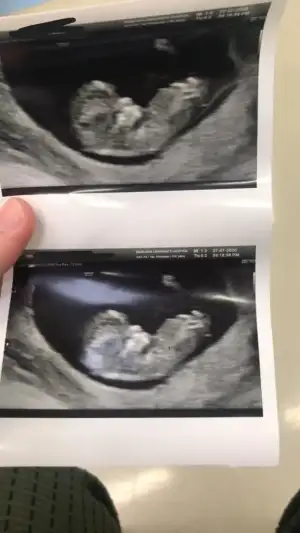

benim miniğime de yorum yapııııın Ikra meyra Ikra meyra

Cnm arkadaşımın bebeğini yorumlarmısın Ikra meyra Ikra meyra

• 14B85633-8D4F-4452-BB5B-DE9F2F4309D2.webp

14B85633-8D4F-4452-BB5B-DE9F2F4309D2.webp

20,1 KB · Görüntüleme: 91